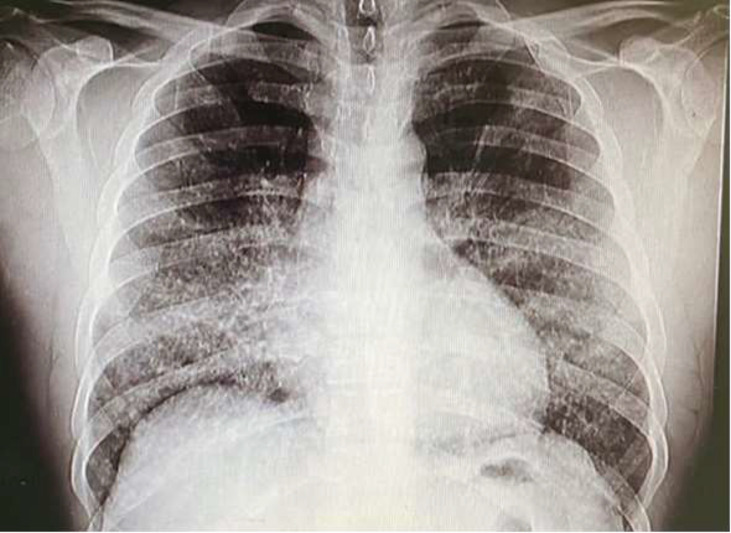

Background: Pulmonary alveolar proteinosis (PAP) is a rare disease caused by the accumulation of surfactant in the lung's alveoli, as a result of malfunction in the cleaning function of alveolar macrophages. The major symptoms include cough and dyspnea. Computed tomography scan usually reveals crazy-paving pattern. Lung biopsy confirms the diagnosis by showing accumulations of periodic acid-schiff-positive lipoproteinaceous materials.

Case presentation: In this report, we present a middle-age man with progressive dyspnea on exertion, and frequent cough with no noteworthy medical history. The results of initial examinations and laboratory tests were non-diagnostic, so imaging studies were requested for the patient. After imaging and suspecting PAP as a differential diagnosis due to results of high resolution computed tomography, a transbronchial biopsy was performed to confirm the diagnosis. Then, according to the histopathology reports, the diagnosis of PAP was made. During the biopsy procedure, the patient developed pneumothorax, and accurate treatment approaches were considered for this complication.